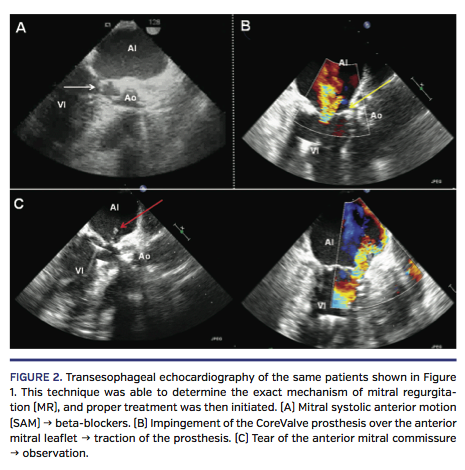

With respect to the mechanism of occurrence of significant MR, angiography was not able to determine the mechanism in any of the cases (Figure 1), while TEE ascertained the mechanism in 100% of cases. One case (9% of the total cases of MR) developed grade IIB significant MR due to mechanical asynchrony because of the appearance of a new left branch block, which was transitory. Three cases (27%) were due to an “impingement” of the prosthesis on the anterior leaflet of the

mitral valve because of low implantation of the prosthesis. The problem was resolved by repositioning the device in the direction of the ascending aorta prior to definitive release. In 2 cases (18%), the mechanism was the appearance of an anterior systolic movement of the mitral valve with the dynamic obstruction of the left ventricle outflow tract and moderate-severe MR immediately after the valvuloplasty (Figure 2), which resolved after the administration of intravenous beta-blockers. In 1 case (9%), after balloon valvuloplasty and prior to prosthesis implantation, a laceration of the anterior commissure of the mitral valve resulted in grade III MR (Figure 2). After implantation of the aortic percutaneous prosthesis and subsequent improvement of the hemodynamic conditions, the degree of MR was reduced at the end of the procedure to grade III. In 4 cases (36%), the mechanism was attributed to a functional cause, ie, the transitory alteration of the left ventricular function during the release of the device, which continued to diminish progressively during the succeeding minutes.

In our study, 2 cases of MR were due to the anterior systolic movement of the mitral valve leaflets secondary to a dynamic obstruction of the left ventricular outflow tract. This etiology has been described after surgery for severe aortic stenosis;14 however, to the best of our knowledge, it has not been reported by other authors in important studies of TAVI, nor has it been described in the recommendations mentioned above for the use of echocardiography in the implantation of this type of prosthesis. In our study, the frequency of this complication has not been negligible, and it seems important to report it as a mechanism of occurrence of MR that should be considered when this type of procedure is performed, as TEE is essential at the point of diagnosis and offers good guidance during the pharmacological management of the patient.

In treating these patients, management was performed depending on the MR mechanism diagnosed by TEE and varied from treatment with beta-blockers for the mitral [systolic anterior movement] to traction on the not-yet-completely released prosthesis in cases where mechanism was the impingement,16 and observation and a conservative attitude in cases where it was due to a functional mechanism or the development of a new transitory left branch block. In the case of the laceration of the mitral anterior commissure, the improvement in hemodynamic conditions and the partial reduction of regurgitation suggested a “wait and see” attitude.